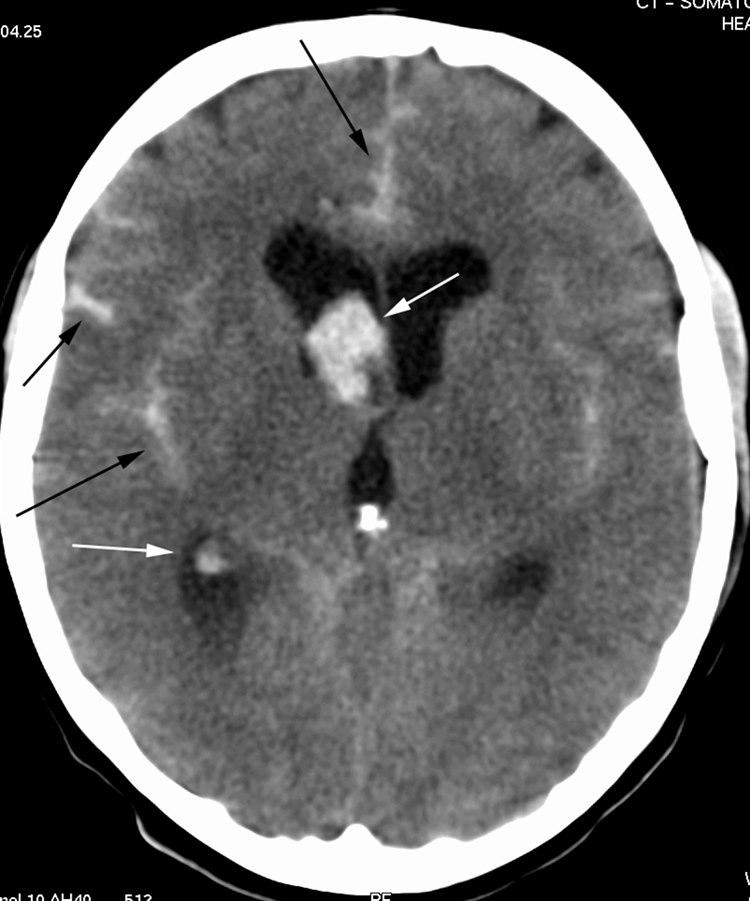

CT axialbilde uten kontrast

Blod (lyse områder) i høyre sideventrikkel (hvite piler), mellom hemisfærene frontalt og i fissura Sylvii på begge sider (svarte piler). Kalk i corpus pineale (intenst hvitt).